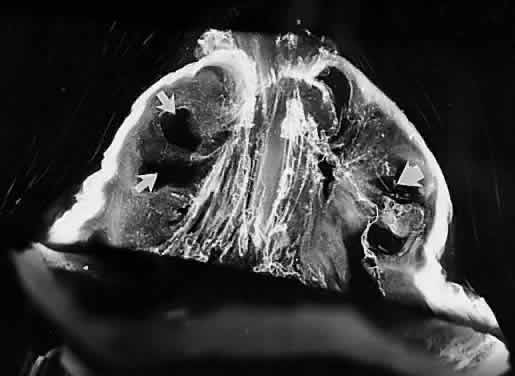

Although vitreous is the largest structure within the eye, comprising 80% of its volume, our knowledge of vitreous structure and function is perhaps the least of all ocular tissues. Historically, investigations of vitreous structure have been hampered by two fundamental difficulties: first, any attempts to define vitreous morphology are attempts to visualize a tissue that is invisible by design (Fig. 1).1 Considerable barriers must be overcome to adequately study the structure of an invisible tissue. Second, the various techniques that were used previously to define vitreous structure were fraught with artifacts that biased the results of these investigations. Thus, as noted by Baurmann2 and Redslob,3 histologic studies performed during the nineteenth and early twentieth centuries were flawed by the use of tissue fixatives that caused the precipitation of what we recognize today as the glycosaminoglycan (GAG) hyaluronan (HA; formerly called hyaluronic acid).

Fig. 1. Vitreous from a 9-month-old child. The sclera, choroid, and retina were dissected off the vitreous, which remains attached to the anterior segment. Because of the young age of the donor, the vitreous is almost entirely gel. Thus, the structure is solid and maintains its shape, although situated on a surgical towel exposed to room air. A band of gray tissue can be seen posterior to the ora serrata. This is peripheral retina that was firmly adherent to the vitreous base and could not be dissected away without disrupting the vitreous base. (Courtesy of the New England Eye Bank, Boston, MA)